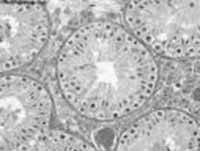

Histológicamente se observan varias estructuras en el testículo del adulto. En su parenquima se observan los túbulos seminíferos (figura 2) en una red de conductos conectados con el epidídimo y que en total suman cinco o seis metros. Comenzando en la cola del epidídimo se ve una estructura tubular de 30 centímetros llamada canal deferente, que termina en el conducto eyaculatorio, cerca de la próstata. El semen se va madurando durante los doce días de tránsito a través del epidídimo y los espermatozoides –allí depositados hasta el momento de la eyaculación- adquieren motilidad sostenida.

– Túbulos seminíferos. Allí se encuentran células reproductoras en diferentes etapas de maduración; Dichas células tubulares están rodeadas de una membrana basal. La espermatogénesis está regulada por la FSH/LH en presencia de testosterona y por el sincitio de Sertoli.

– Sincitio de Sertoli. Diseminadas entre las células germinales, se ven unas células multi-nucleadas muy ricas en glicógeno, que se encargan de la nutrición de las espermatogonias.

– Células intersticiales de Leydig. Ricas en citoplasma y con núcleo prominente, también están esparcidas en el espacio inter-tubular; se encargan de la producción de andrógenos. Su función está regulada por la hormona estimulante de las células intersticiales o ICSH, que es la misma LH.

Para la función reproductora normal se necesita que estos tres tipos de células se encuentren muy próximas.

Figura 2. Histología del testículo